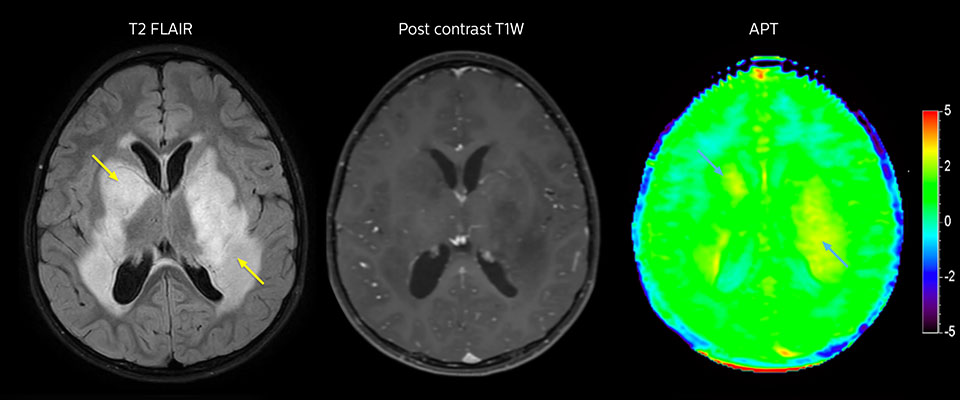

Niedrig differenziertes Gliom bei einem 5-jährigen Patienten mit Neurofibromatose 1. Diese niedrig differenzierte Läsion zeigt auf kontrastverstärkten Bildern keine Anreicherung, aber ein mittelgradiges APT-Signal. Die Stabilität der Läsion über die Zeit bestätigt, dass es sich um eine pathologische Veränderung niedriger Differenzierung handelt.

Der Radiologe John Curran, MD, war leitender Forscher bei der Untersuchung der APT-gewichteten Bildgebung am Phoenix Children's Hospital. „Bis jetzt wurde APT bei etwa 70 MRT-Studien an Kindern mit Gehirntumoren eingesetzt, und wir haben bereits einige ermutigende Erstergebnisse“, so John Curran, MD, Radiologe am Phoenix Children's Hospital (PCH). „Wir brauchen grösser angelegte Studien mit mehr Patienten, um die Korrelation genau zu ermitteln. Jedoch muss es keine 100%ige Korrelation sein, um bei Nachuntersuchungen von Hirntumoren nützlich zu sein, da wir auch FLAIR und andere Bilder betrachten. Das Ziel ist, etwas zu identifizieren, bevor es zu gross wird, und zu ermitteln, ob es eine neue Operation oder neue Therapie erfordert, und wenn wir etwas Verdächtiges sehen – im Gegensatz zu einem definitiven Rezidiv – ist das oft nicht eine Sache des sofortigen Handelns, sondern der Nachuntersuchung.“

Die an der Studie beteiligten Ärzte des PCH sind vorsichtig optimistisch, dass APT-gewichtete Bildgebung irgendwann den Einsatz von Kontrastmitteln bei pädiatrischen Patienten deutlich reduzieren kann. „Wenn wir APT als angemessenen Ersatz voranbringen können, wäre es insbesondere bei unseren Gehirntumorfällen in der Nachuntersuchung von grossem Vorteil“, sagt Dr. Curran. „Die Verwendung von Kontrastmitteln wird in unserer allgemeinen Neuroradiologie-Bildgebung streng überwacht, und Kontrastmittel wird nur verabreicht, wenn es wirklich erforderlich ist. Daher konzentriert sich unsere Studie darauf, zu bestimmen, ob wir in der Zukunft APT nutzen können, um den Einsatz von Kontrastmitteln zu verringern.“

Dr. Curran verglich bei Kindern mit einer Anamnese von Hirntumoren APT-gewichtete Bildgebung mit kontrastverstärktem MRT. „In vielen Fällen haben wir gesehen, dass APT positiv ausfällt, wenn kontrastverstärkte T1-gewichtete Bildgebung positiv ist. Deshalb versuchen wir, zu beurteilen, ob diese Beziehung stark genug ist, um APT unter bestimmten Umständen möglicherweise zu verwenden, anstatt einem Kind Kontrastmittel zu verabreichen. In der Studie wird APT-Forschungssoftware genutzt, die in einer Forschungszusammenarbeit von Philips entwickelt wurde.